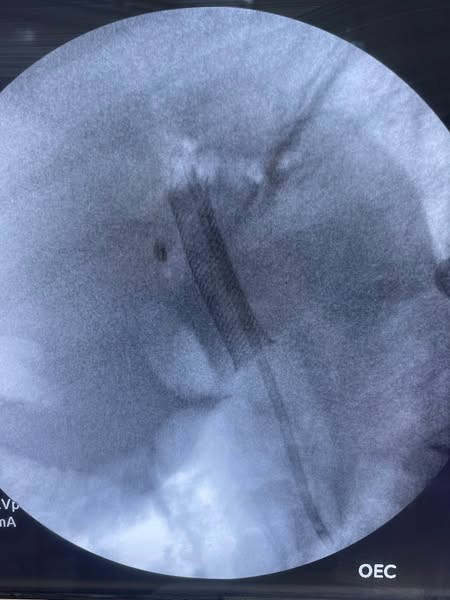

Extraction was done with dormia basket and washing then we use foreign body and fluoroscopy for removal of PCMS.

Insertion of double pigtail stent with good biliary flow.

Fig 1, Fig 2, Fig 3, Fig 4, Fig 5, Fig 6

Figure 4